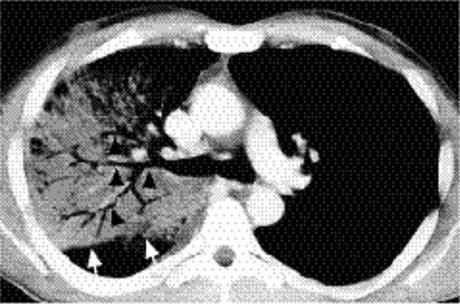

Cavitating consolidation (Figs. 5.13 and 5.14) suggests bacteria or fungi. S. aureus, Klebsiella, anaerobes, and Mycobacterium tuberculosiscommonly cause cavitation. Pneumatoceles may result in a similar appearance (Fig. 5.15) and suggest S. aureus or S. pneumoniae.Emphysematous bullae within consolidated lung may mimic cavities.

Figure 5.14 Cavitary pneumonia (C) at computed tomography.